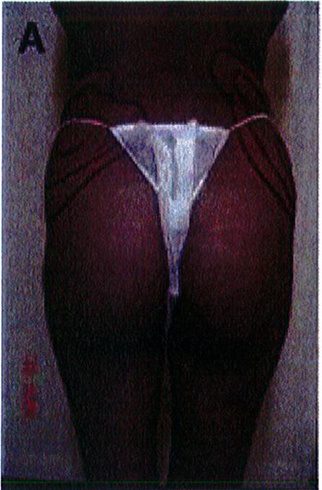

Để tránh tình trạng quá ngắn hoặc quá dài của vùng mông (hay còn gọi là mông dài/ngắn) thì tác giả đã kết hợp một phép đo đơn giản trước phẫu thuật, đo khoảng cách từ mào chậu phía sau tới đường ngang đi qua trung điểm nếp liên mông (khoảng cách A) và từ đường ngang đó tới nếp lằn mông (khoảng cách B) (Hình 1) đế tính vị trí chuẩn xác của khối im- plant.

Để tránh tình trạng phần mông trên được nâng lên quá mức, khoảng cách A thông thường phải gấp đôi khoảng B để có thể phù hợp cho nâng mông dưới cơ.

Nếu khoảng cách A ngắn hơn, nên sử dụng mặt phẳng trong cơ để tạo điều kiện cho khối im- plant được đẩy xuống thấp hơn 1 chút, giúp đạt được kết quả thẩm mỹ lý tưởng.

Hình. 1. Đánh giá trước phẫu thuật để lựa chọn bệnh nhân với mặt phẳng im- plant phù hợp.

Hình. 2. Bệnh nhân với khung chậu quá rộng hoặc quá ngắn đều không phù hợp với implant mông.

Hình. 3. (A-H) Tiền phẫu, chu phẫu và sau hậu phẫu 6 tháng của một bệnh nhân nữ 38 tuổi đươc ghép túi đôn mông với thể tích 330 cm3.

Hình. 4. (A-I) Hình ảnh tiền phẫu, chu phẫu và sau hậu phẫu 11 tháng của một phụ nữ 25 tuổi đã được thực hiện hút mỡ vùng éo, hông và sau xương vùng, đồng thời ghép khối cấy thể tích 270cm3.

Hình. 5. (A-F) Hình ảnh tiền phẫu và sau hậu phầu 4 tháng của bệnh nhân 67 tuổi, ghép khối implant thể tích 300 cm3.